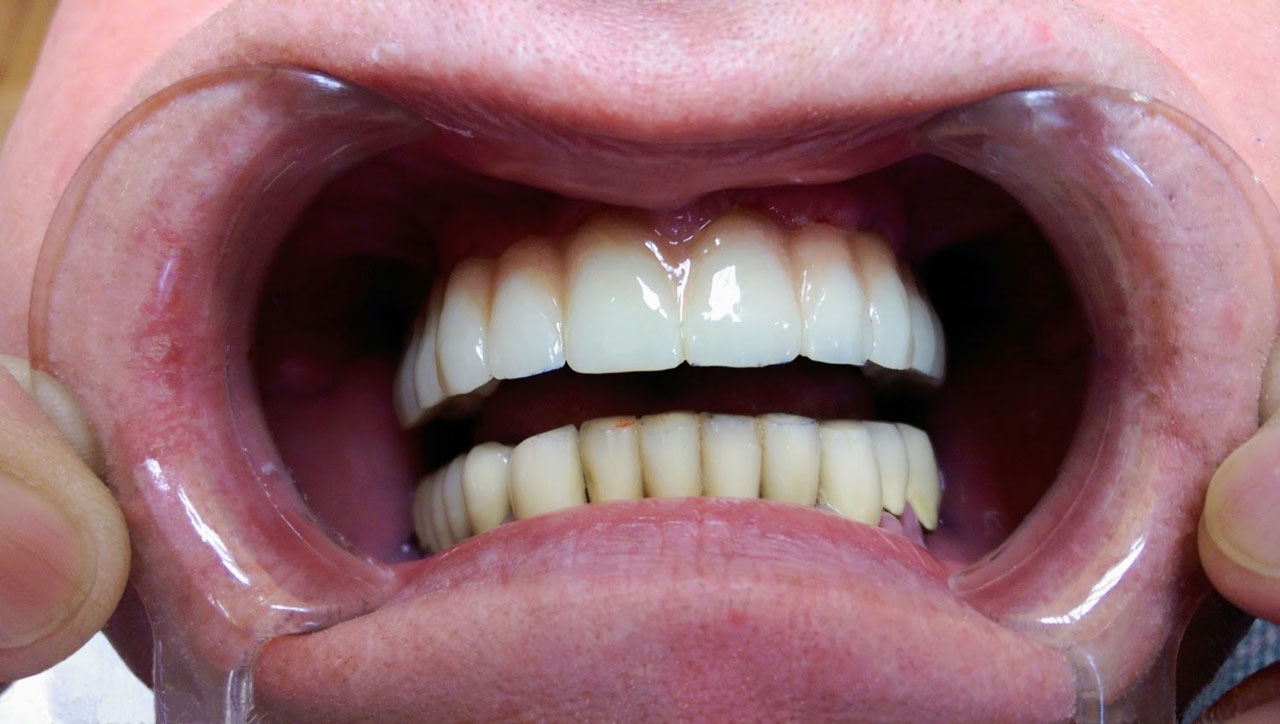

Sikerét mindenekelőtt a gyorsaságának köszönheti, hiszen a mai rohanó világban kinek van ideje, kedve fogatlanul otthon ülni heteket, hónapokat a fogpótlásra várva? Az Ihde implantációs eljárás során a páciens azonnal, de legkésőbb 72 óra múlva egy rögzített (tehát nem mozgó, nem kivehető) pótlással hagyja el a rendelőt. Ez az egyedülállóan gyors eljárás annak köszönhető, hogy azonnal tudunk implantálni szinte bárhova, akár foghúzás után is, továbbá a művelet nem jár nagy feltárásokkal, nincs szükség csontbeültetésre, így a gyógyulás folyamata is nagyon gyors és a beültetés technikájának köszönhetően maximum 72 óra múlva a korona is feltehető. Tehát ennyi idő alatt foga lesz a betegnek és az implantátum azonnal terhelhetővé is válik.

Természetesen, az Ihde Azonnal Terhelhető Implantátum Rendszer alkalmazása speciális szaktudást igényel, így elengedhetetlen az orvosok gondos és folyamatos képzése. Ez, illetve a kiváló minőségű svájci alapanyagok és a sok évtizedes, precíz, innovatív gyártási technológia együttese adja, hogy a cég kiemelkedően magas (98,2%-os) sikert ér el, az Ihde implantátumok bent maradásának mérésekor.